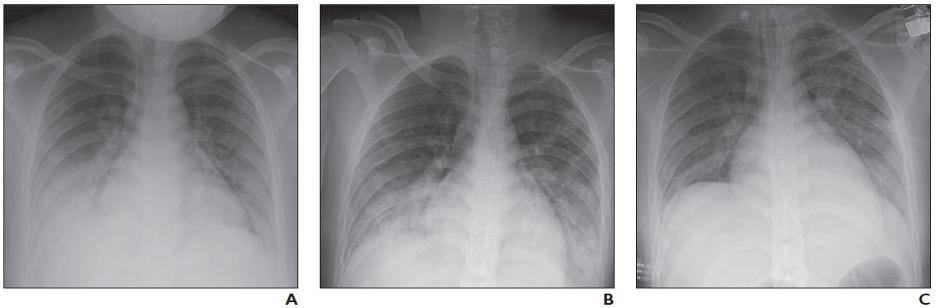

Covid 19 Pneumonia Progression And Regression Radiology Case Radiopaedia Org